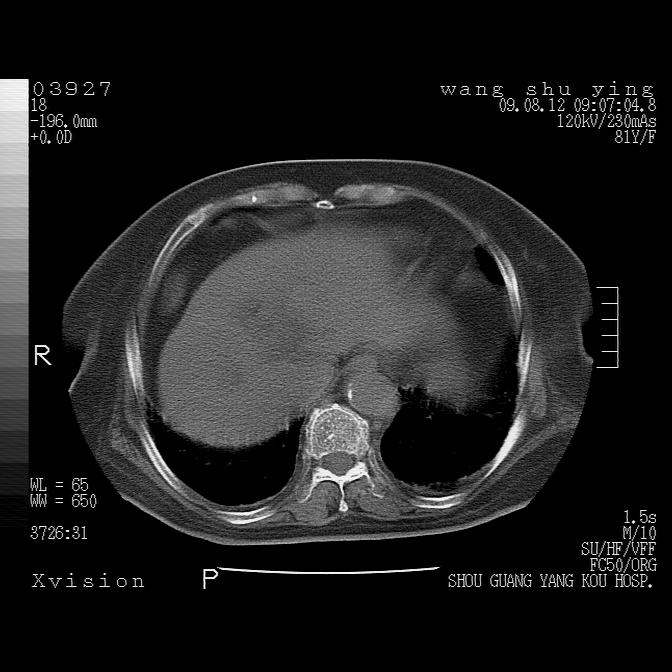

以下是引用帅河马在2009-8-12 12:59:00的发言:[br]两肺感染性病变伴双侧胸膜肥厚。[br]左侧甲状腺腺瘤不除外。[br]腹水+心包积液。[br][br][本贴已被 帅河马 于 2009-8-12 13:14:32 修改过]

以下是引用sdzyy在2009-8-12 18:17:00的发言:[br]两肺感染性病变伴双侧胸膜肥厚。[br]左侧甲状腺腺瘤不除外。[br]腹水+心包积液。[br]支持

以下是引用随光逐影在2009-8-12 19:42:00的发言:[br]1)两肺感染性病变伴双侧胸膜肥厚。2)不排除左侧甲状腺腺瘤。3)肝脏占位性病变;建议行进一步检查。